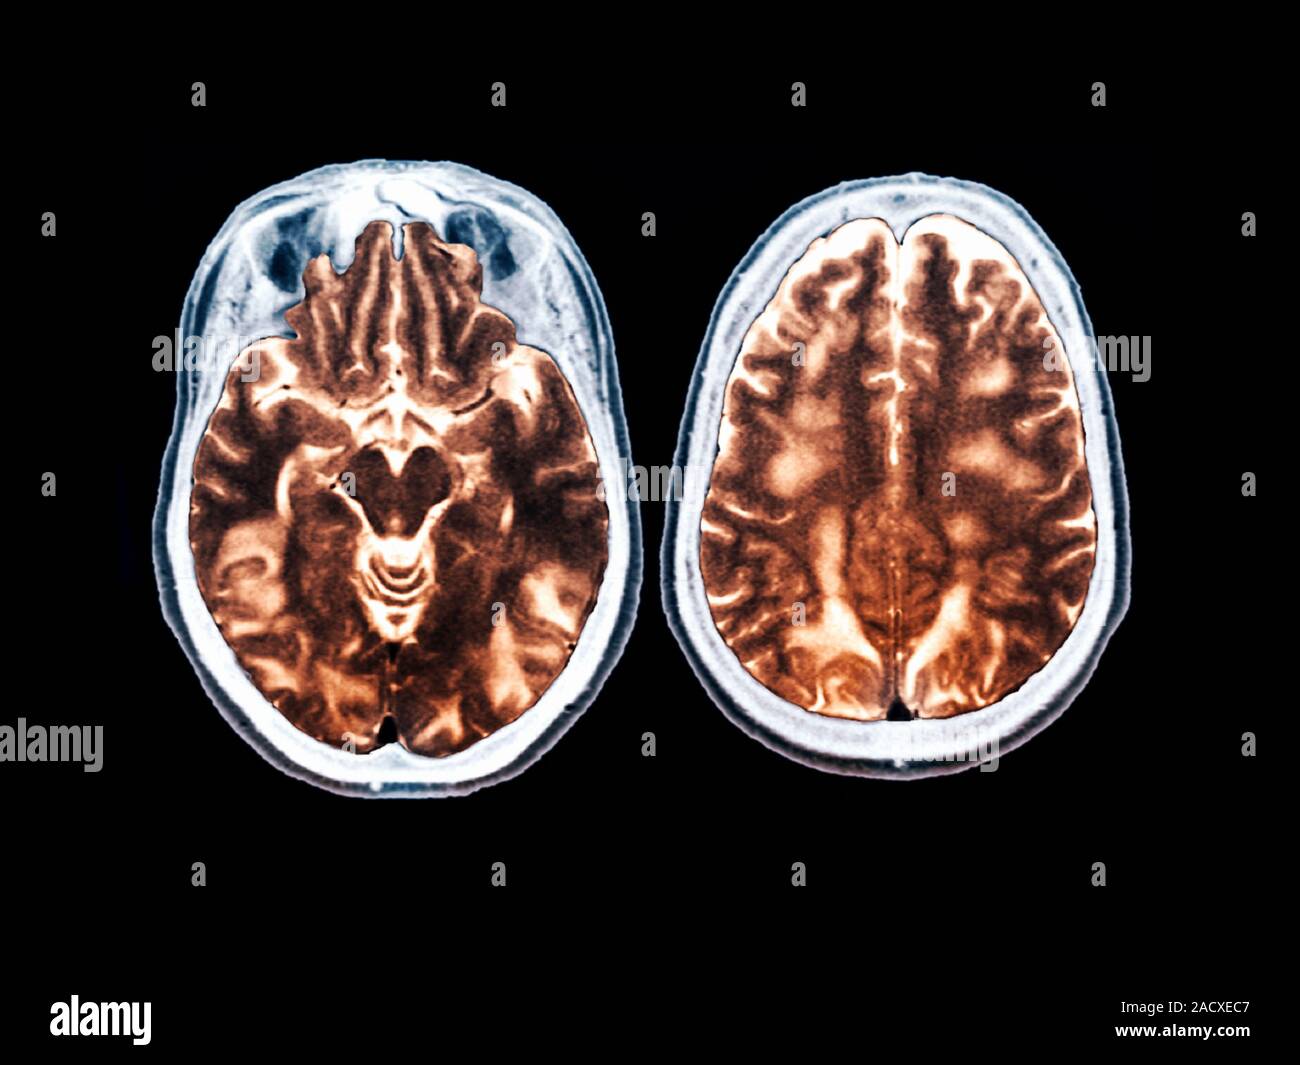

From www.alamy.com

Eclampsia. Coloured resonance imaging (MRI) scan of the brain of a 27 year old woman Eclampsia Radiology Clinical and neuroradiographic correlates and insights into the pathogenesis. Preeclampsia, defined as the new onset of hypertension, peripheral edema, and proteinuria after at least 20 weeks of gestation in a woman previously without. Posterior reversible encephalopathy syndrome is associated with eclampsia. E levated l iver enzymes and. We assessed the distribution and. It is considered a severe and life. Eclampsia Radiology.

Eclampsia. Coloured resonance imaging (MRI) scan of the brain of a 27 year old woman Eclampsia Radiology Preeclampsia, defined as the new onset of hypertension, peripheral edema, and proteinuria after at least 20 weeks of gestation in a woman previously without. Posterior reversible encephalopathy syndrome is associated with eclampsia. Clinical and neuroradiographic correlates and insights into the pathogenesis. E levated l iver enzymes and. It is considered a severe and life. We assessed the distribution and. Eclampsia Radiology.